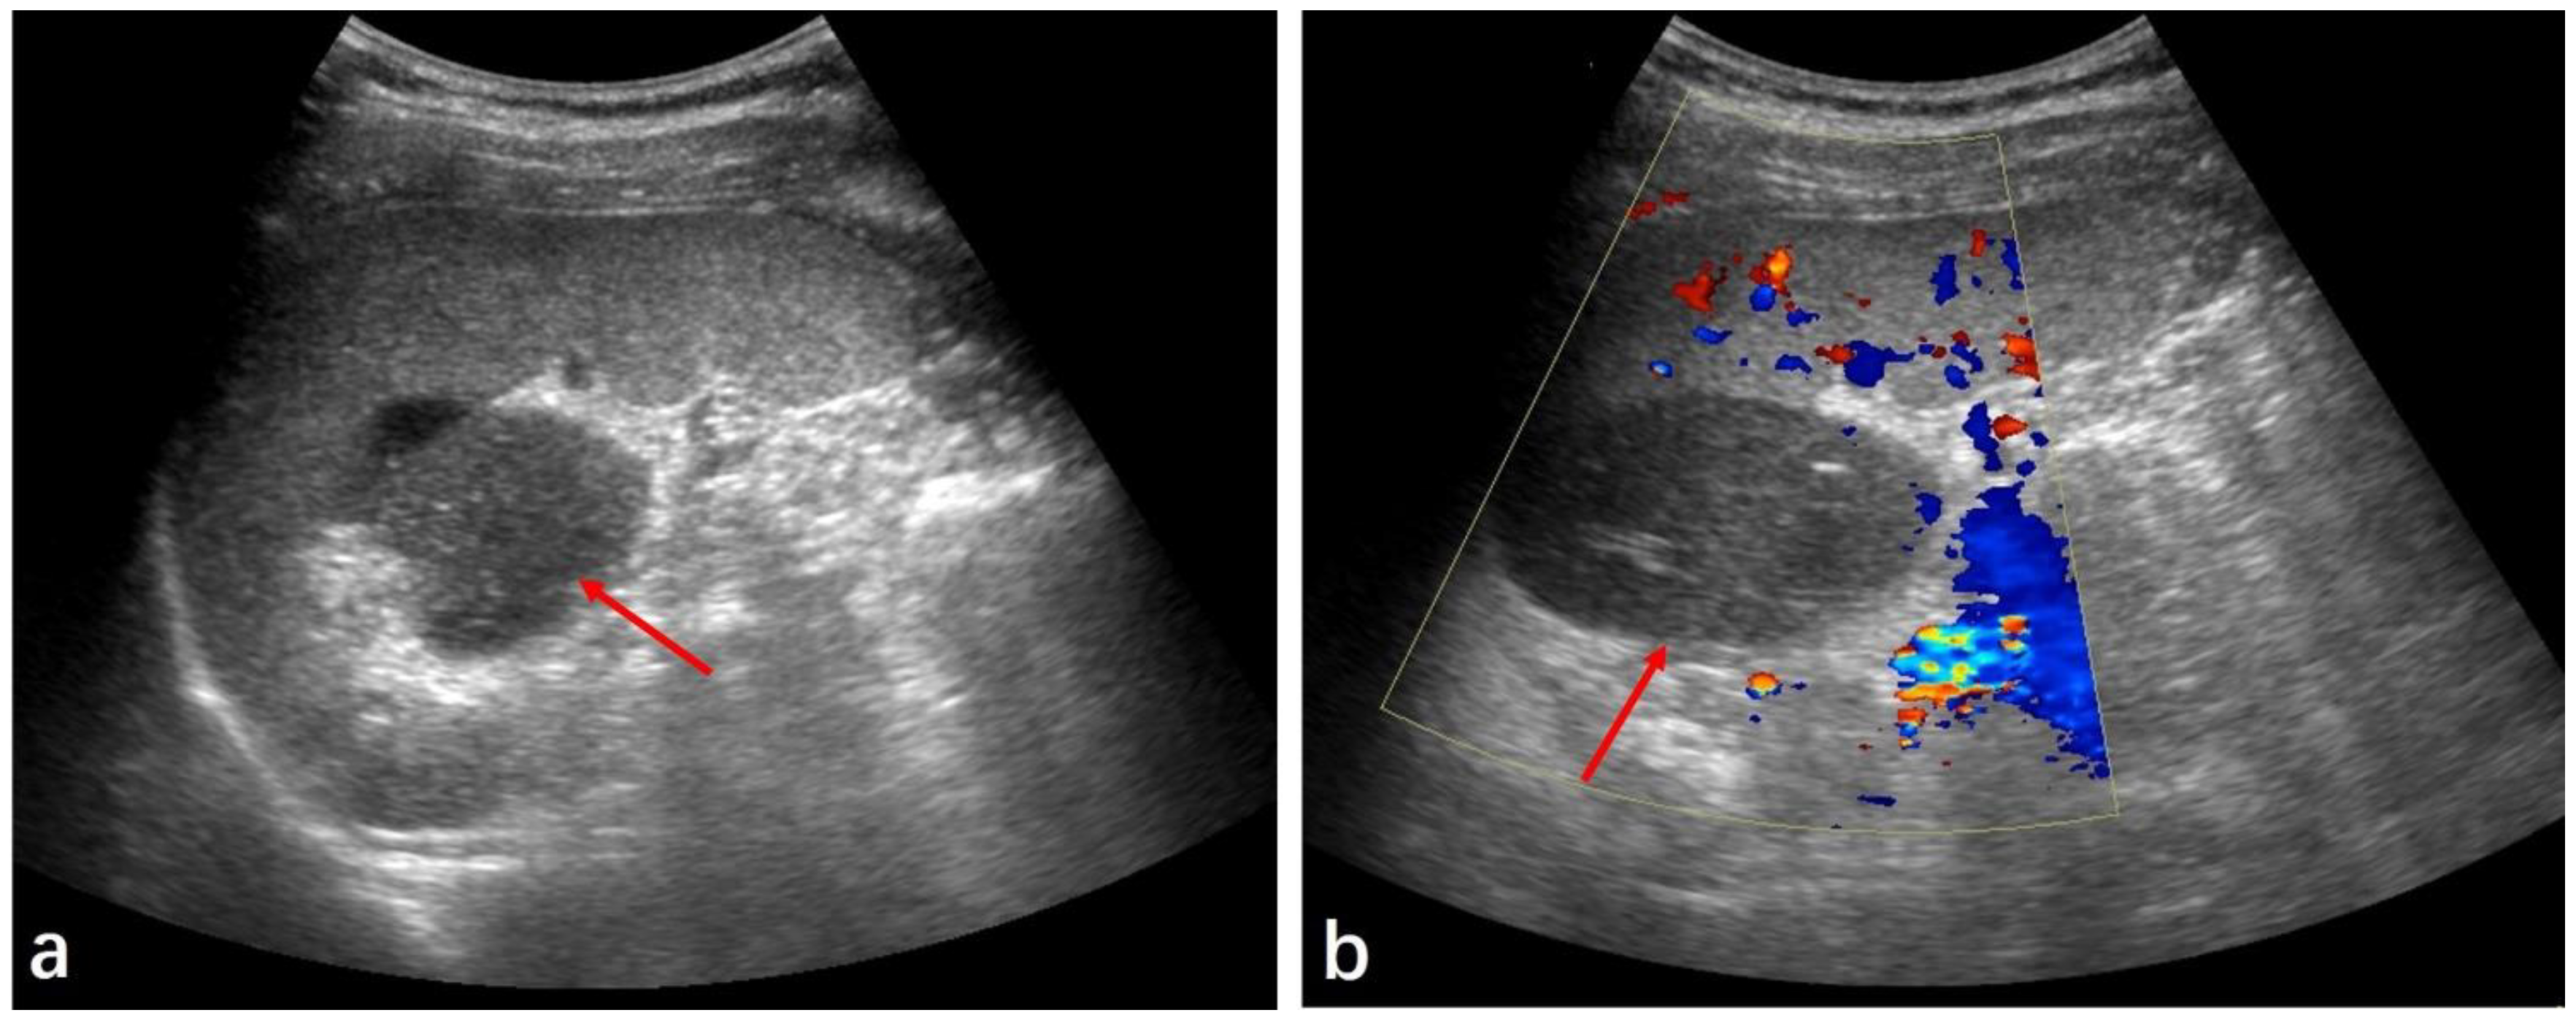

2. Case Presentation